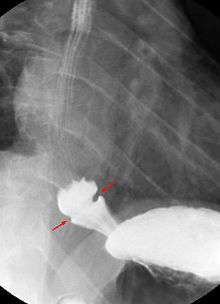

A Schatzki ring is usually diagnosed by esophagogastroduodenoscopy or barium swallow. Endoscopy usually shows a ring within the lumen of the esophagus which can be of variable size (see picture). The ring is usually located a few centimetres above the gastro-esophageal junction, where the esophagus joins the stomach. Schatzki rings can often resemble a related entity called an esophageal web. Esophageal webs also contain extra mucosal tissue, but do not completely encircle the esophagus.